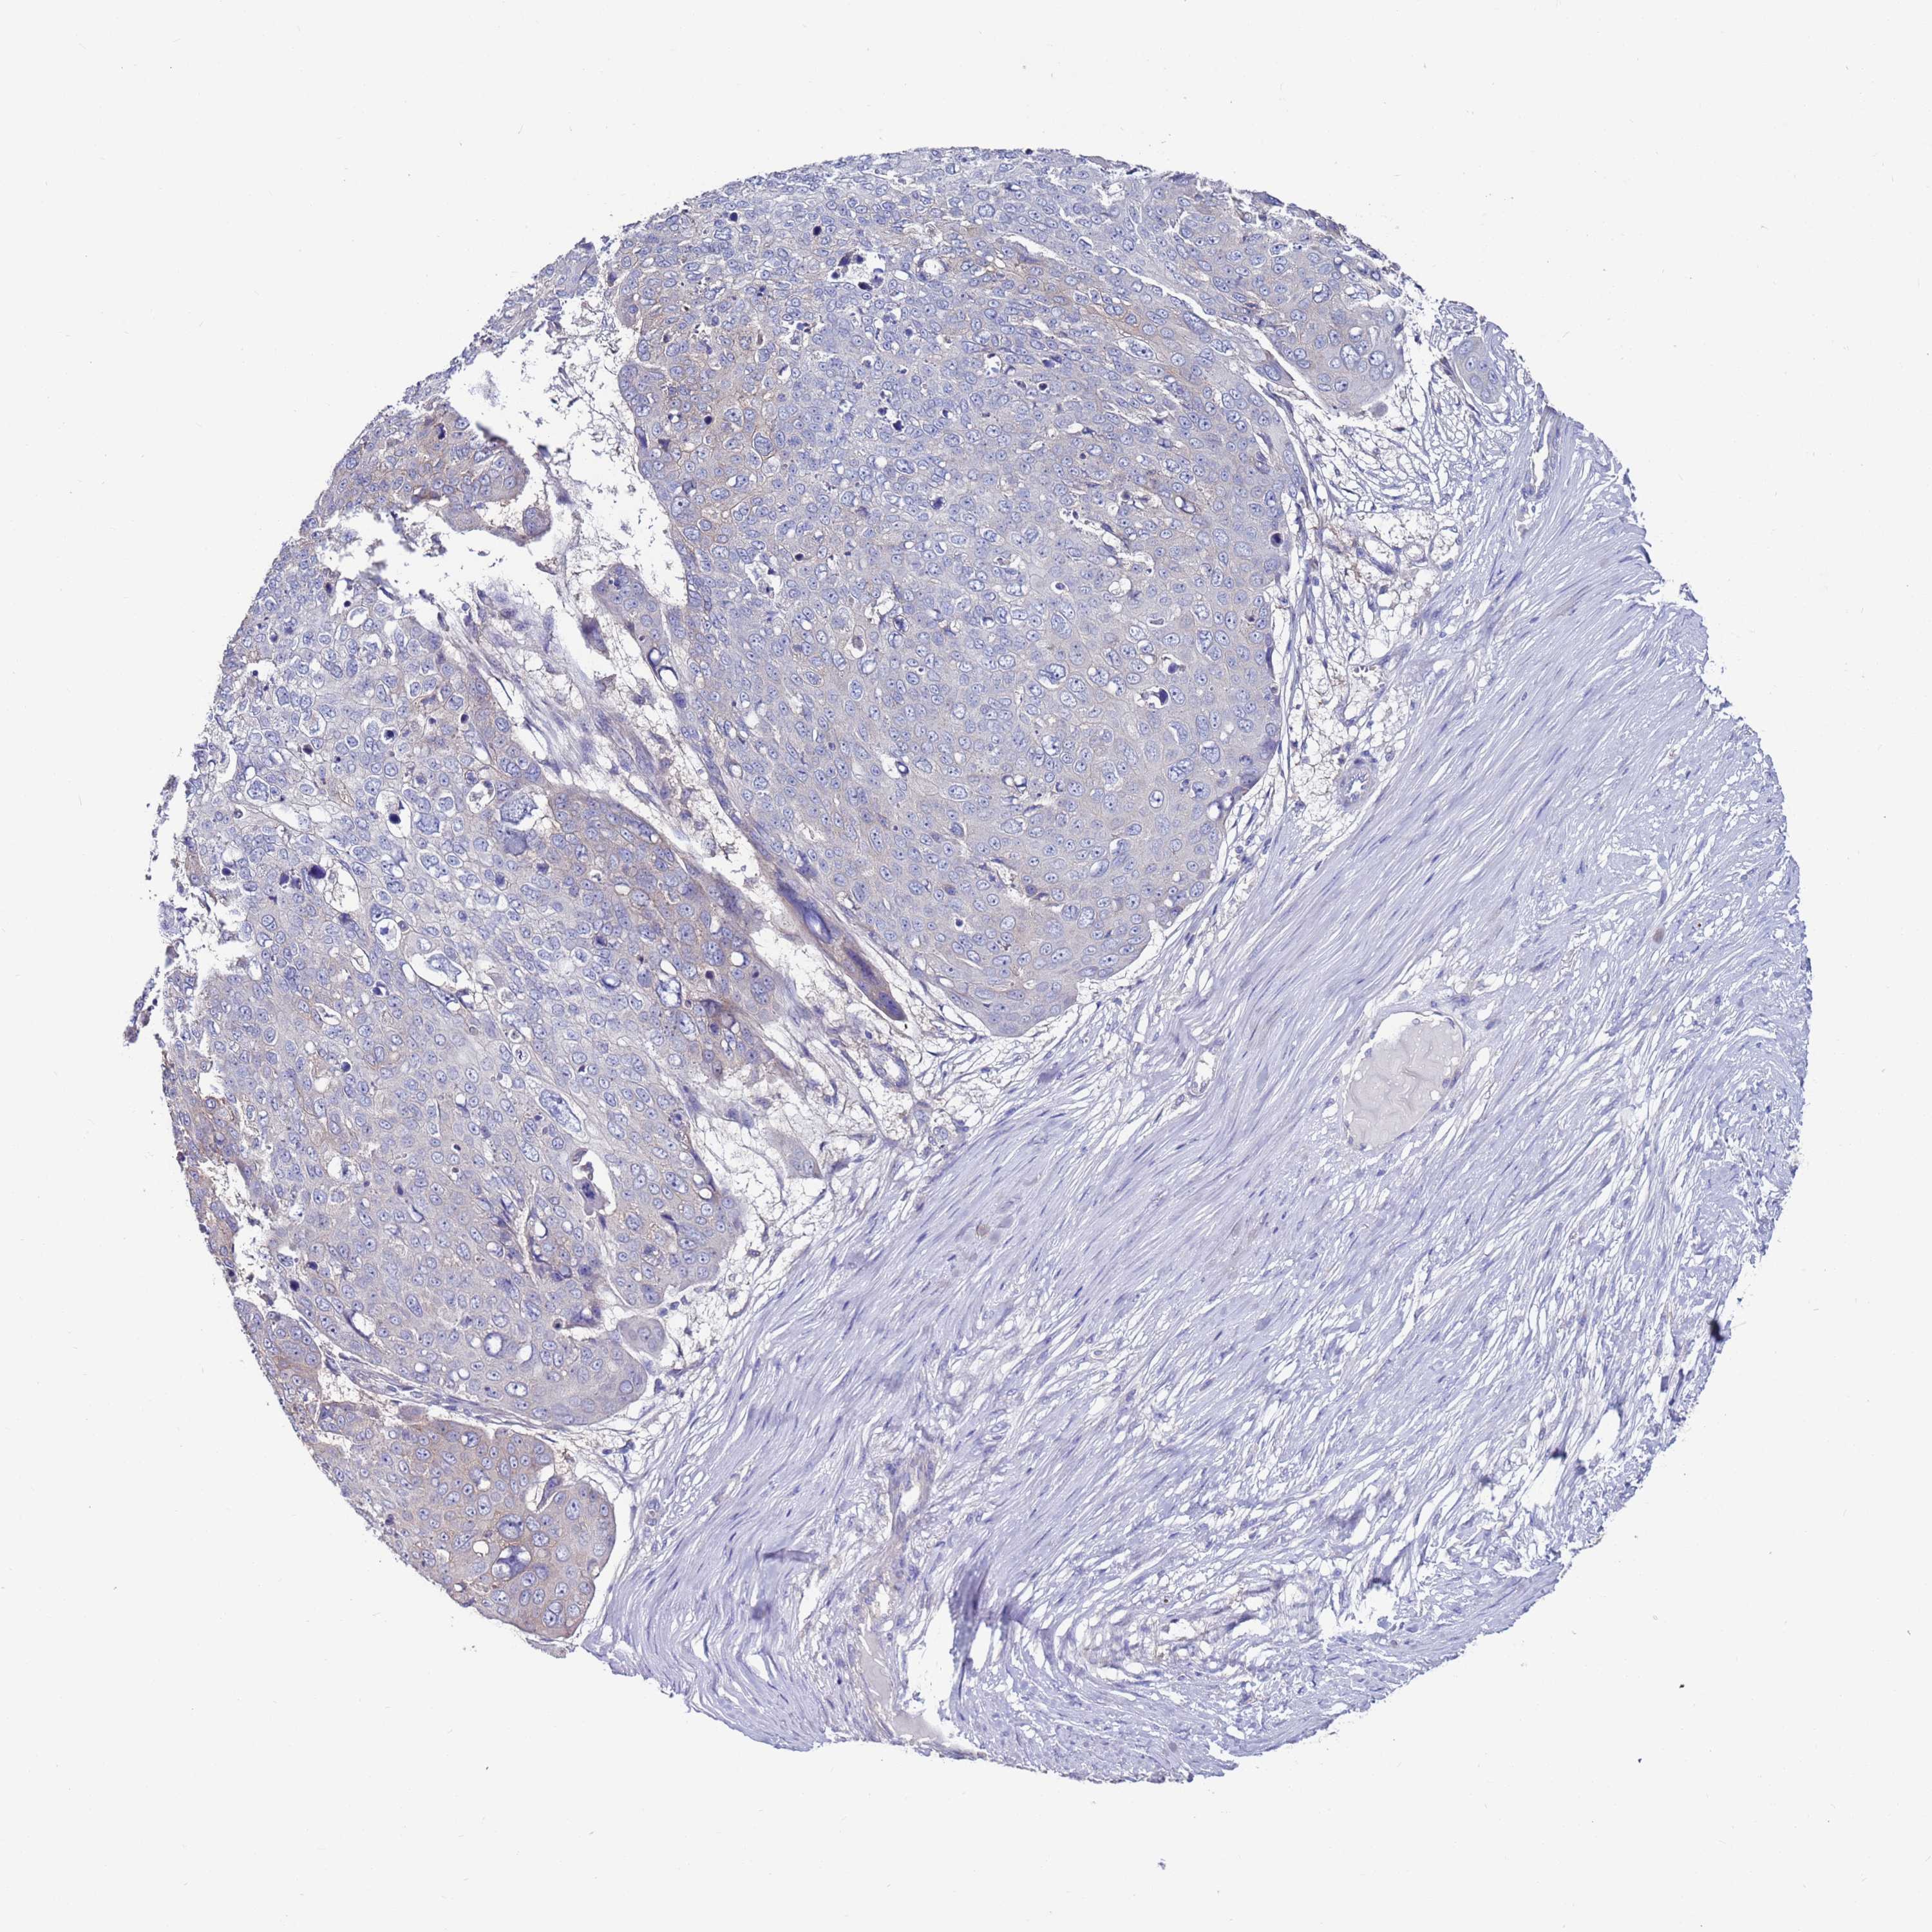

Basal cell and squamous cell cancer

SKIN CANCER - Protein expressioni

A mouse-over function shows sample information and annotation data. Click on an image to view it in a full screen mode. Samples can be filtered based on level of antibody staining by selecting one or several of the following categories: high, medium, low and not detected. The assay and annotation is described here.

Antibody stainingi

Antibody staining in the annotated cell types in the current human tissue is reported as not detected, low, medium, or high, based on conventional immunohistochemistry profiling in selected tissues. This score is based on the combination of the staining intensity and fraction of stained cells.

Each image is clickable and will lead to virtual microscopy that enables deeper exploration of all samples and also displays staining intensity scores, fraction scores and subcellular localization as well as patient and tissue information for each sample.

Antibody HPA047136

Staining

High

Medium

Low

Not detected

Intensity

Strong

Moderate

Weak

Negative

Quantity

>75%

75%-25%

<25%

None

Location

Nuclear

Cytoplasmic/membranous

Cytoplasmic/membranous,nuclear

Squamous cell carcinoma, NOS